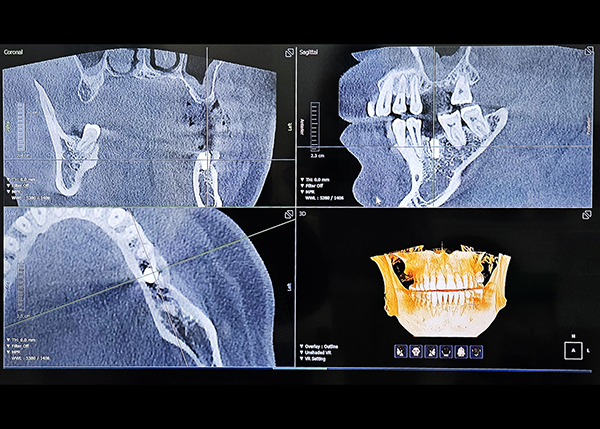

다양한 디지털 진단 장비를 활용

정밀 진단 및 치료계획으로 오차 줄인 진료

성공적인 임플란트 식립을 위해서는 무엇보다 정밀한 진단이 선행되어야 합니다. 3D-CT, 구강 스캐너, 3D Printer 등 다양한 디지털 장비를 이용하여 잇몸뼈, 신경 위치 등을 정확하게 파악해 오차를 최소화하고, 통증 및 출혈을 줄여 더욱 안전하고 편안한 임플란트 식립이 가능합니다.

디지털 정밀 진단

일반 임플란트

치아 상태 및 신경의 위치를 2D(평면)으로만 확인이 가능해

정확한 진단이 어려움

3D CT를 통한 컴퓨터 분석

현재 턱 뼈와 잇몸의 상태를 3차원 입체 영상으로 확인이 가능해

정밀 진단에 따른 오차 없는 수술이 가능